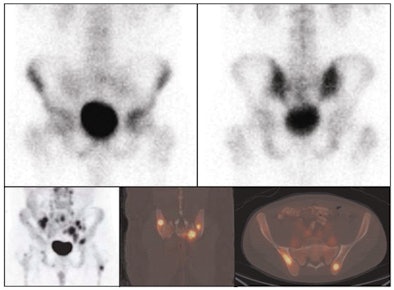

| Images of a 23-year-old man with relapsed nodular sclerosing Hodgkin's lymphoma; FDG-PET shows a greater extent of disease involvement. The top images show anterior (left) and posterior (right) spot views of bone scan, which indicate mildly increased uptake in the left acetabulum and right inferior pubic ramus. The bottom panel illustrates FDG-PET posterior maximal intensity projection (left), coronal fusion (center), and transverse fusion (right) images, with many focal areas of abnormal uptake in the pelvis and proximal femurs. |